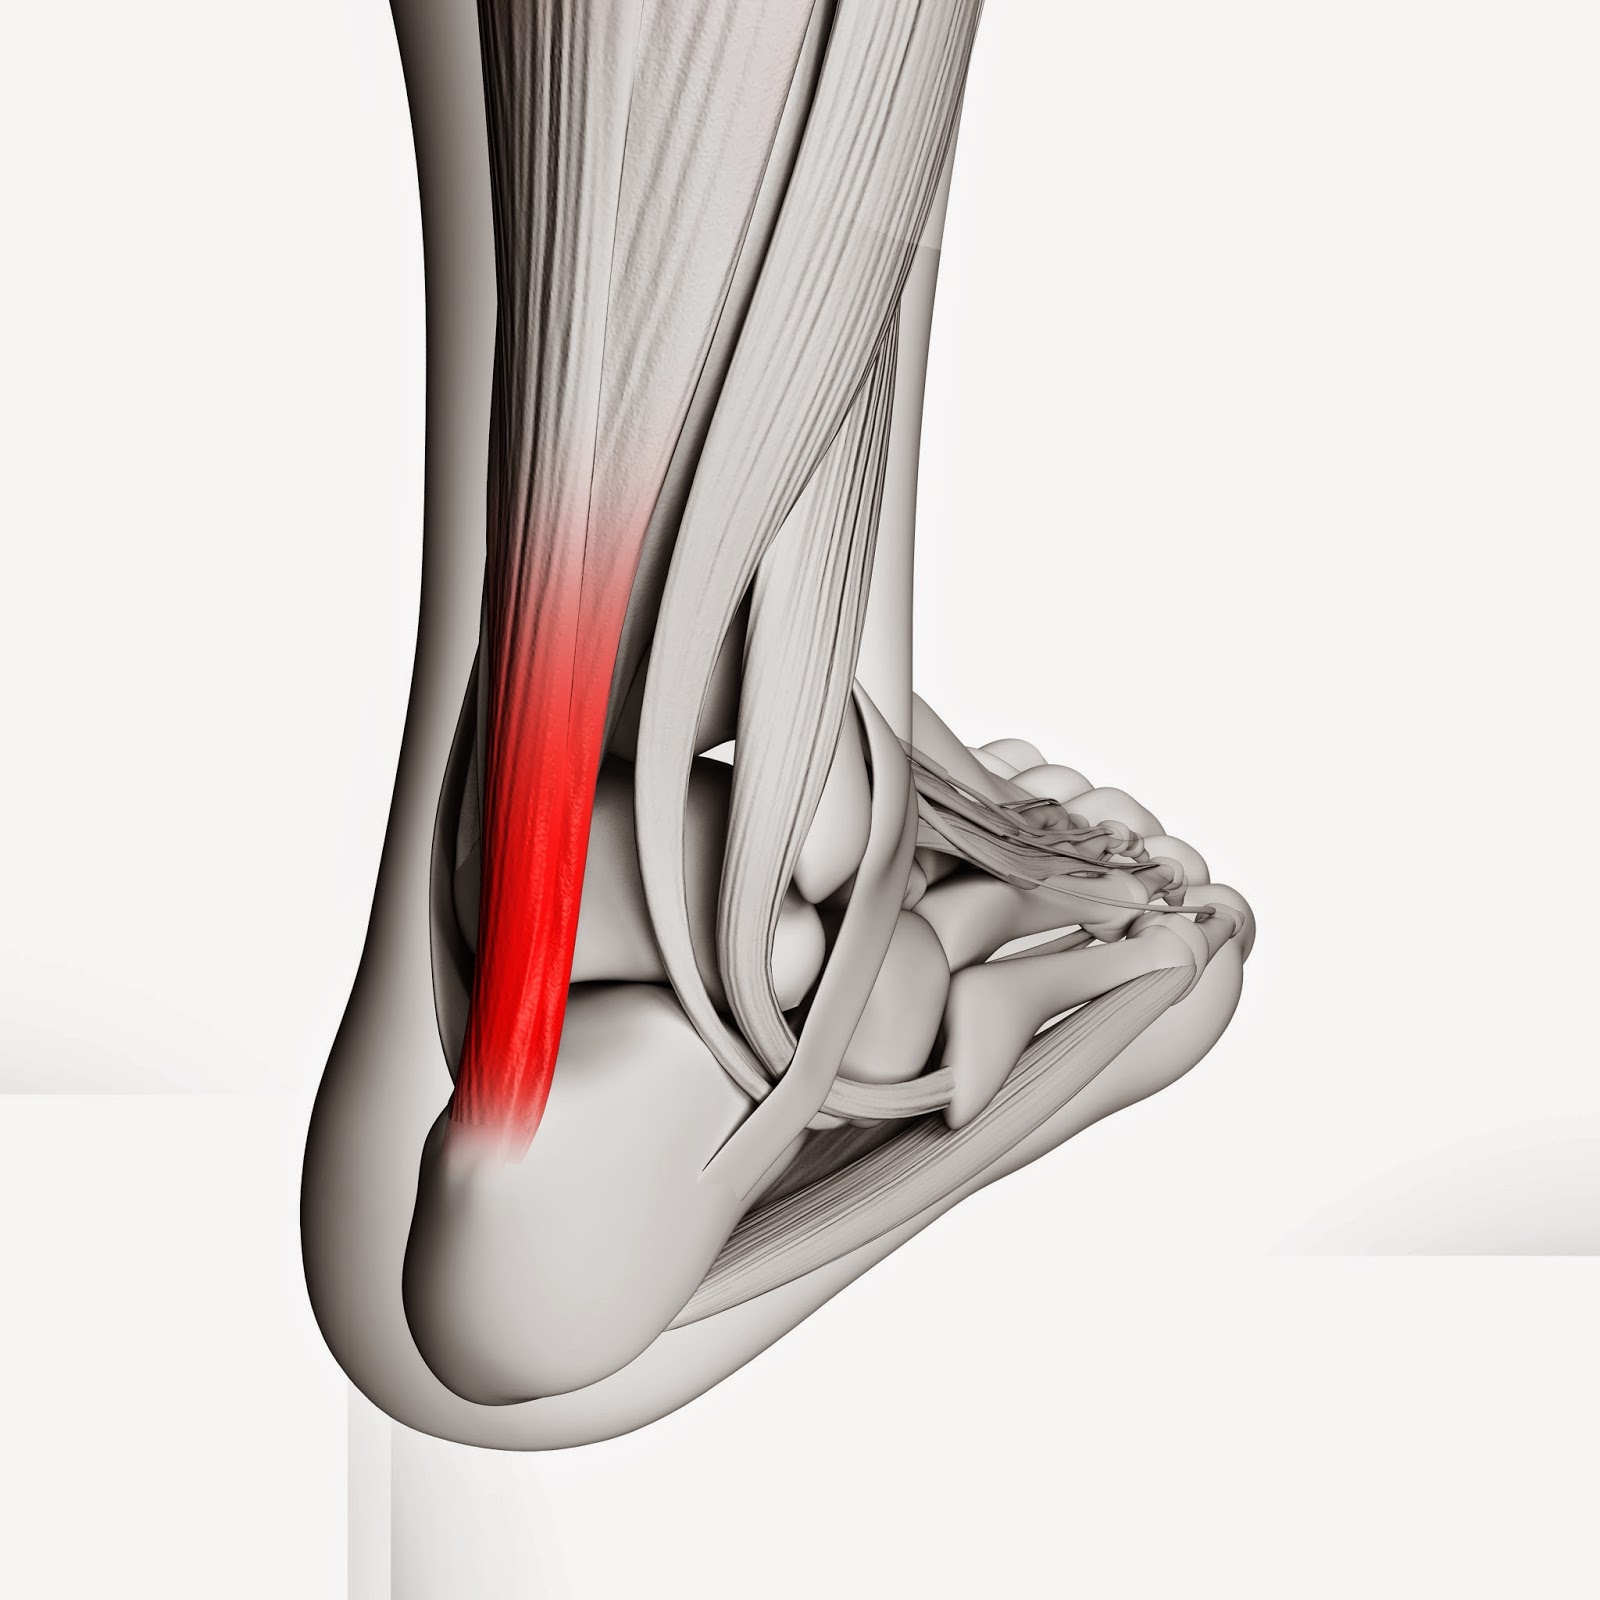

Achilles Tendonitis Basics | Florida Orthopaedic Institute

Feel Better Now Series – How To Treat Achilles Tendinitis – Best home …